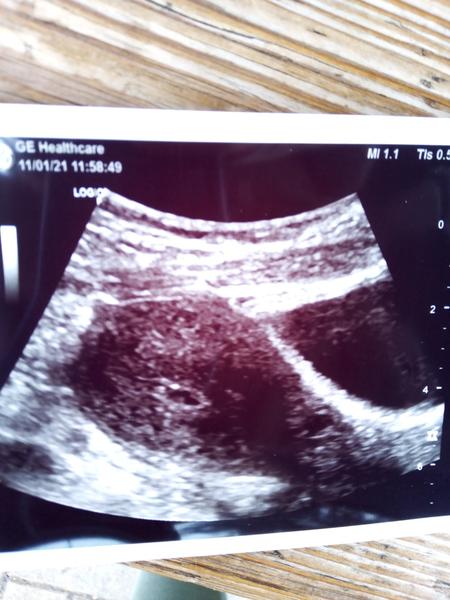

@stepankova2 tak jsem byla u p.dr. na ultrazvukuuu nešlo ještě nic vidět , vzala krev volala jsem druhý den na výsledky tak podle krve těhotná jsem , v pondělí mám jít znova na ultrazvuk , mám obavy aby to bylo vše v pořádku , nevím jestli jsem šla dost brzo aby šlo něco vidět na ultrazvuku a nebo je nějaký problém , někdo nějakou zkušenost ? Podle kalkulačky bych měla být 4tt , mám docela strach ,

@agneska7 mela jste pravdu byla jsem a neviděla na ultrazvuku ještě nic tak odebrala krev volala druhý den a potvrdila těhotenství, v pondělí jdu opět na ultrazvuk, jsem docela vystrašená mám strach jestli je vše v pořádku , a nebo jestli jsem šla fakt brzo k p.Dr

@vaalllllllli8i já tam byla 5.1 řekla mi že je to málinke ale je to tam, podle kalkulačky bych měla být 7tt

@vaalllllllli8i je to moc brzo 😉 u mě např. Nebylo nic vidět ani v 6+1 TT ,,,, určitě to bude dobré 😉🍀

@vaalllllllli8i to si jdes pro knizku teda brzo ja ji dostala at v 11tt..🙂ale foto z prvni kontroly kdy mi potvrdili tehu mam taky🙂